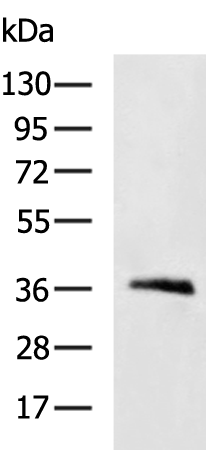

分类: 科研抗体货号: P10678别名:应用: WB,IHC反应种属: Human, Mouse, Rat